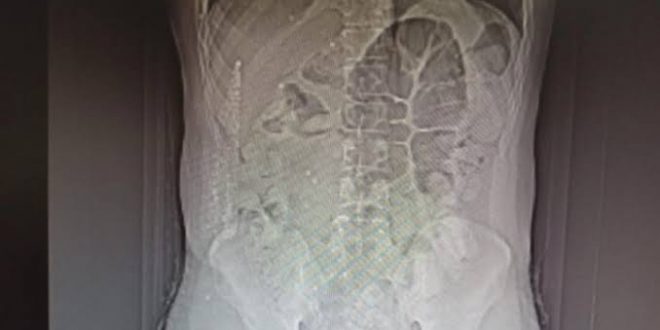

Tomografi çekimi yapılan İran uyruklu zanlının mide ve bağırsağında 64 parça halinde 711 gram afyon sakızı bulunduğu tespit edildi.